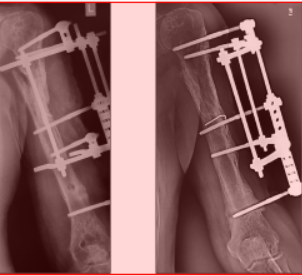

Выезд травматолога-ортопеда, рентгенолога Александра Валерьевича Дидковского.